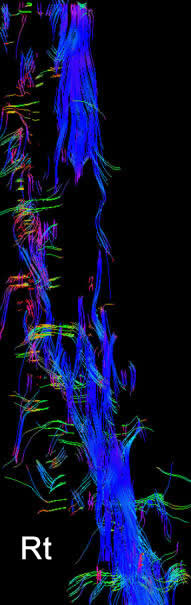

Fibertraking is misleading in pathological anatomy in the brain and spinal cord. This case failed to show the real thickness and distribution of the spinal cord fibers.

Fibertraking of the spinal cord around the lesion in anterior first, left second, posterior third and the last is right projections showing the fibers more concentrated in the left side, despite the fact the patient has weak left foot.